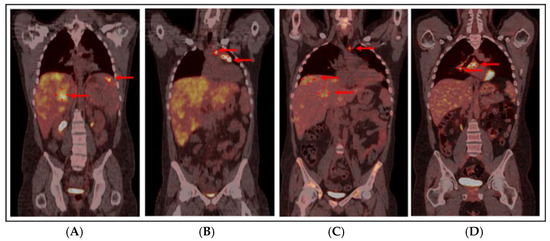

Background and Clinical Significance: Histiocytic sarcoma (HS) is a rare and aggressive form of malignant histiocytosis, often associated with poor prognosis. The diagnosis and management of HS are challenging due to the complexity of its pathogenesis, molecular profile, and the unclear cellular origin [...] Read more.

Background and Clinical Significance: Histiocytic sarcoma (HS) is a rare and aggressive form of malignant histiocytosis, often associated with poor prognosis. The diagnosis and management of HS are challenging due to the complexity of its pathogenesis, molecular profile, and the unclear cellular origin of histiocytic neoplasms, compounded by the limited literature on treatment strategies. Case Presentation: We report the case of a young patient with HS localized to the lymph nodes, spleen, and liver, who also presented with hemophagocytic lymphohistiocytosis (HLH) documented on bone marrow biopsy. Initial treatment with CHOEP-21 and ICE-21 chemotherapy resulted in only a partial metabolic response, as evidenced by a Fluorodeoxyglucose-Positron Emission Tomography (FDG-PET)/CT scan. Given the aggressive nature of the disease and the presence of HLH, an allogeneic hematopoietic stem cell transplantation (HSCT) from a matched unrelated donor was performed as consolidation therapy, leading to a progressive complete response without significant toxicity. A suspected relapse at 18 months post-transplant was excluded following a mediastinal lymph node biopsy, which revealed a benign intravascular papillary endothelial hyperplasia (IPEH). Over five years post-diagnosis and more than four years after transplantation, the patient remains in complete remission with full functional recovery. Conclusions: This case highlights the diagnostic and molecular challenges of HS and demonstrates the curative potential of early allogeneic HSCT, even when only partial remission is initially achieved. Full article

Show Figures

Figure 1